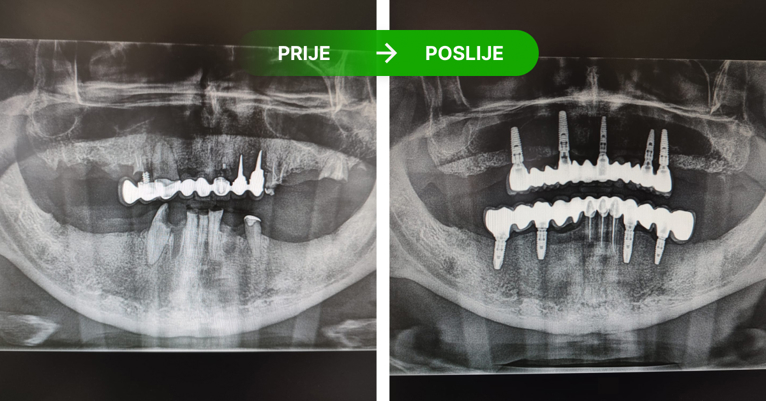

Protetika: prije i poslije. Foto: Dental Centar Jelić

Protetika u kojoj implantati imaju ulogu korjena zuba.

Na četiri ili šest implatanta izrađujemo keramičke mostove